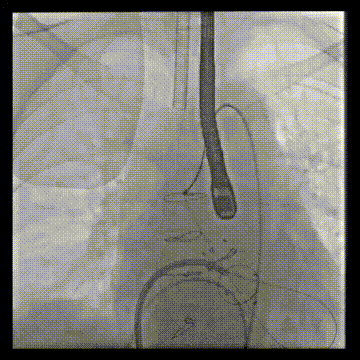

DSA引导下调整瓣膜位置

快速起搏180次/分,23mm+2cc球囊膨胀扩张瓣膜

左室造影显示无PVL